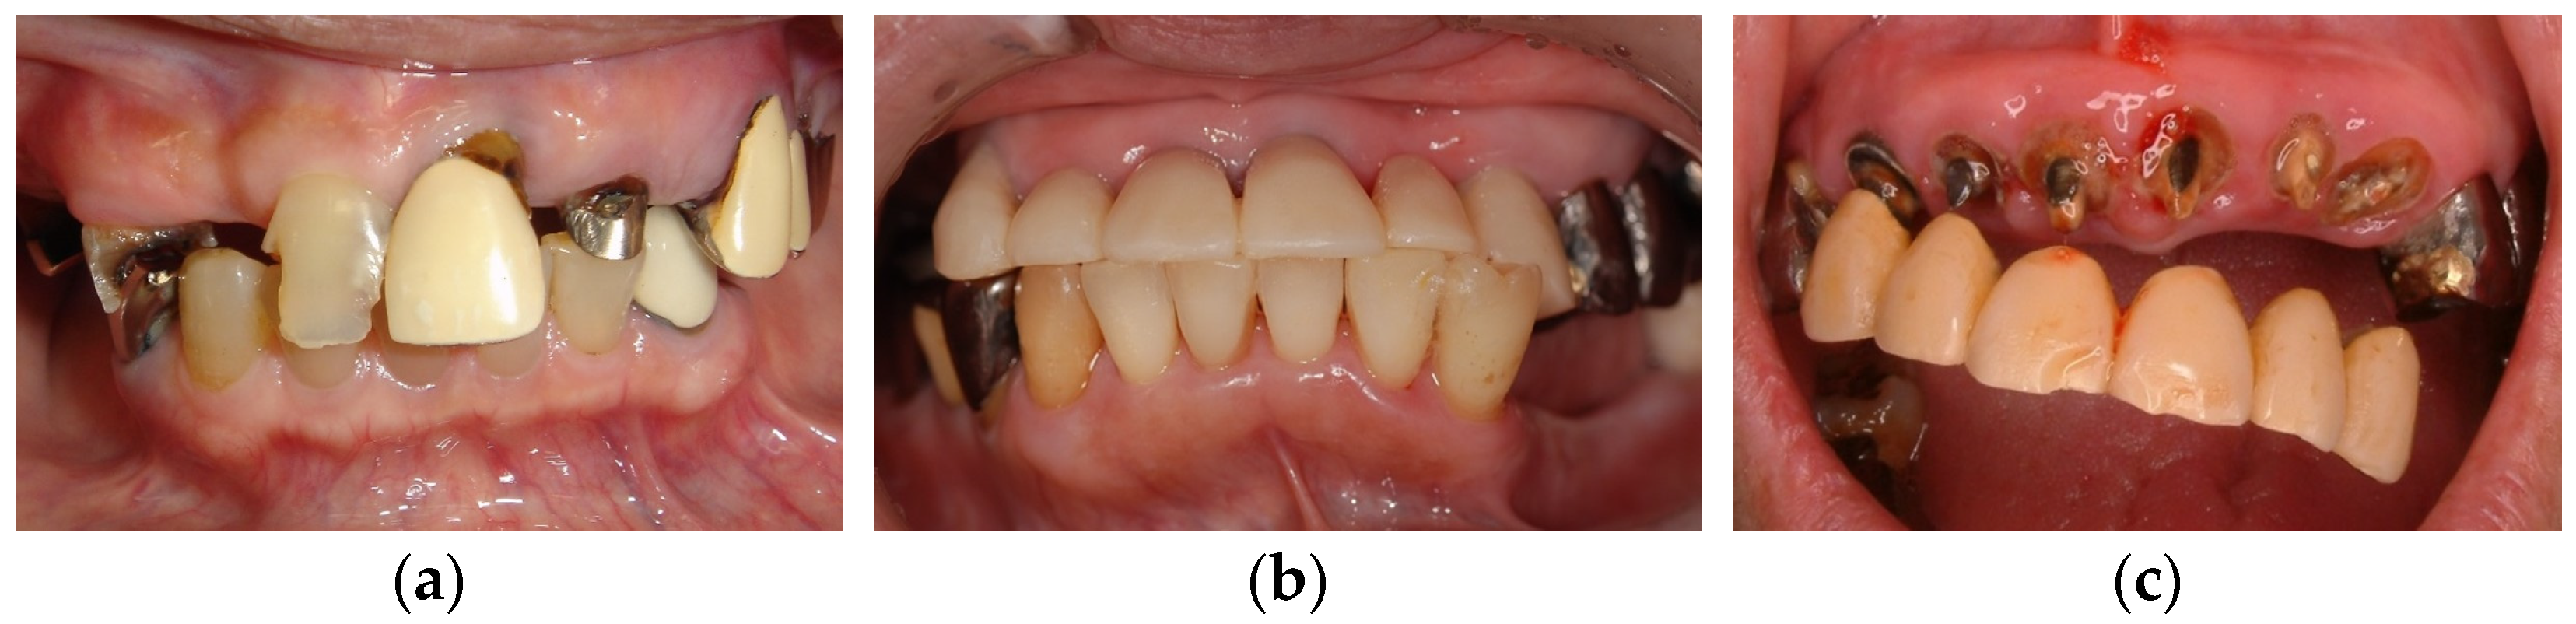

3.3. Clinical Management

Whereas anterior hyperfunction is induced by multiple factors, a loss of posterior occlusal supports and a loss of VDO are considered as primary factors. To prevent and manage anterior hyperfunction, posterior occlusal supports and VDO should be confirmed and must be reestablished if they are disrupted. In addition, supraeruption of the mandibular anterior teeth or inappropriate length of mandibular anterior teeth and subsequent occlusal plane discrepancy may be observed. It is strongly recommended to improve them to manage anterior hyperfunction effectively (Figure 2).

Figure 2. Occlusal plane discrepancy due to mandibular anterior teeth: (a) pre-treatment: occlusal plane discrepancy attributed to mandibular anterior teeth (intercuspal position); (b) pre-treatment: state of mouth opening; (c) post-treatment: adjustment of occlusal plane (intercuspal position); (d) post-treatment: state of mouth opening. Source: the authors.